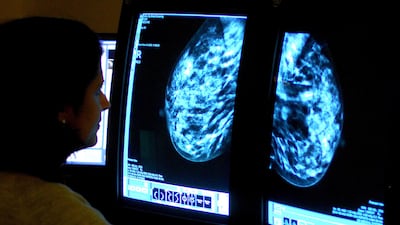

While breast cancer campaigns such as the Pink Caravan continue to boost breast cancer awareness, experts called for a similar national strategy for other cancers like colorectal and lung, particularly targeting non-nationals.